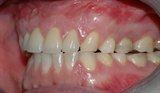

Bildet viser et eksempel på alvorlig tanngnissing.

Man kan se hvordan tennene er svært slitt.